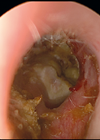

Middle ear reconstruction in children: why, when and how

Every ear in every child is different. Rob Nash discusses the rationale behind reconstructive ear surgery in children and his philosophy on timing and techniques of reconstruction. It is rare for middle ear pathologies to be life threatening. Indeed, it...